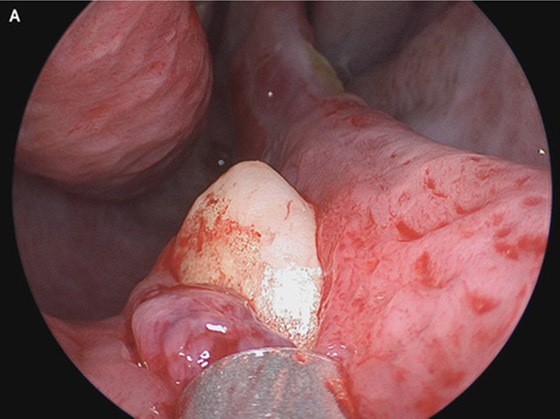

عندما بدأ المريض في الشكوى من ضيق التنفس، أجرى الفحوصات، ووجد الأطباء أنه يعاني من انحراف الحاجز الأنفي، بالإضافة إلى نمو يشبه العظم داخل الأنف. ظهرت هذه المضاعفات غريبة؛ لأن المريض لم يكن يعاني من أي تشوهات في الوجه. ومن أجل الوصول إلى أساس المشكلة، أجرى جراحو الفم والوجه والفكين فحص للأنف من خلال أداة تشبه الأنبوب، ليكتشف الجراحون وجود كتلة بيضاء تبدو كالسن تظهر من داخل فتحة الأنف اليمنى، ويبلغ طول هذا السن 15 مل.